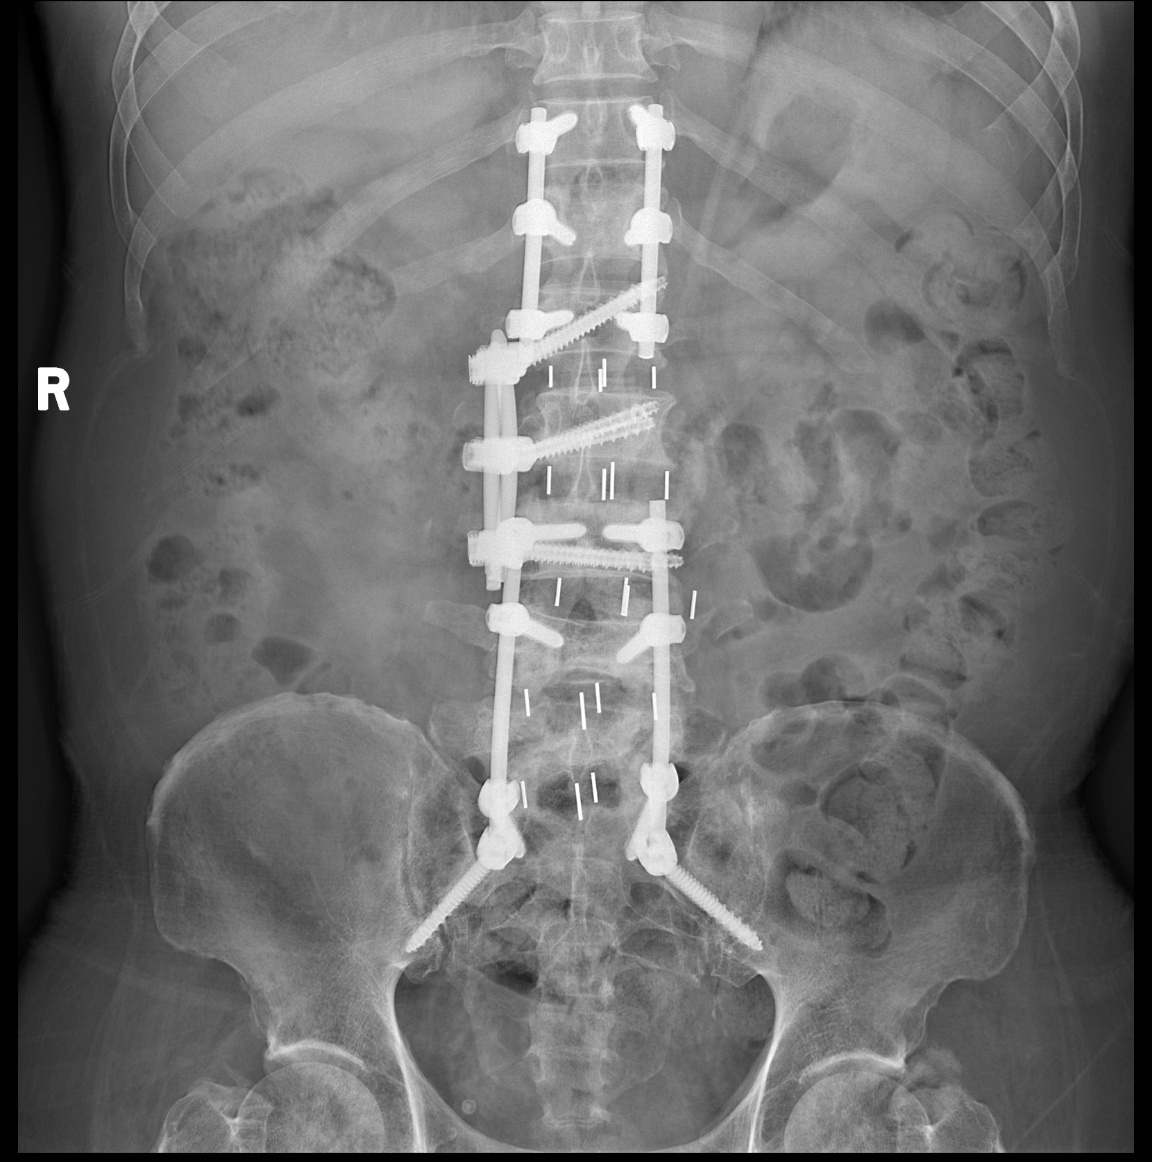

2024年我来到同济光谷院区脊柱微创中心工作,这一年里,我的绝大多数腰椎手术,大部分颈椎手术和小部分胸椎手术都是微创。脊柱微创手术占比,全科室最高。尤其是颈椎微创,应该是这个大区域里做的最多的医生了。做的越多,感觉微创优势越大,内镜是深入手术野的显微镜,创伤小,看的更清楚,病人康复快。 更重要的是,微创让不可能成为可能,化腐朽为神奇。这个患者腰椎感染,腰腿疼痛剧烈,卧床不起两月,有心脏病,肝硬化,腹水,巨脾,消化道溃疡,手术风险极大。患者强烈要求手术,而且抱着不成功便成仁的决心:如果术中术后有生命危险,他拒绝进ICU抢救。这种手术谁敢做? 我做了微创手术,他术后三天就可以坐起来,走路了,看他的微笑。 2025-01-15 18:23